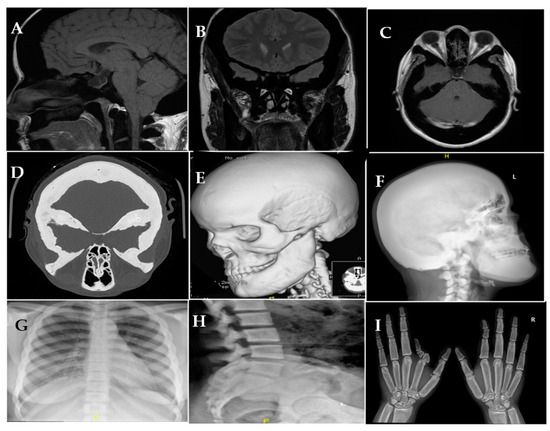

Background and Objectives: Sclerostin is an SOST gene product that inhibits osteoblast activity and prevents excessive bone formation by antagonizing the Wnt signaling pathway. Sclerosteosis has been linked to loss of function mutations in the SOST gene. It is a rare autosomal [...] Read more.

Background and Objectives: Sclerostin is an SOST gene product that inhibits osteoblast activity and prevents excessive bone formation by antagonizing the Wnt signaling pathway. Sclerosteosis has been linked to loss of function mutations in the SOST gene. It is a rare autosomal recessive disorder characterized by craniotubular hyperostosis and can lead to fatal cerebellar herniation. Our aim is to describe the clinical and radiological features and the new underlying SOST mutation in a patient with sclerosteosis. Case: A 25-year-old female who was referred to the endocrine clinic for suspected excess growth hormone. The patient complained of headaches, progressive blurred vision, hearing disturbances, increased size of feet, proptosis, and protrusion of the chin. She had normal antenatal history except for syndactyly. Images showed diffuse osseous thickening and high bone mineral density. Biochemical and hormonal tests were normal. Due to progressive compressive optic neuropathy, optic nerve fenestration with decompression hemicraniotomy was performed. Sclerosteosis was suspected due to the predominant craniotubular hyperostosis with syndactyly. Using peripheral leucocyte DNA, genomic sequencing of the SOST gene was performed. This identified a novel deletion homozygous mutation in the SOST gene (c.387delG, p.Asp131ThrfsTer116) which disrupts sclerostin function, causing sclerosteosis. Conclusions: Discovery of the molecular basis of sclerosteosis represents an important advance in the diagnosis and management of this fatal disease. Full article